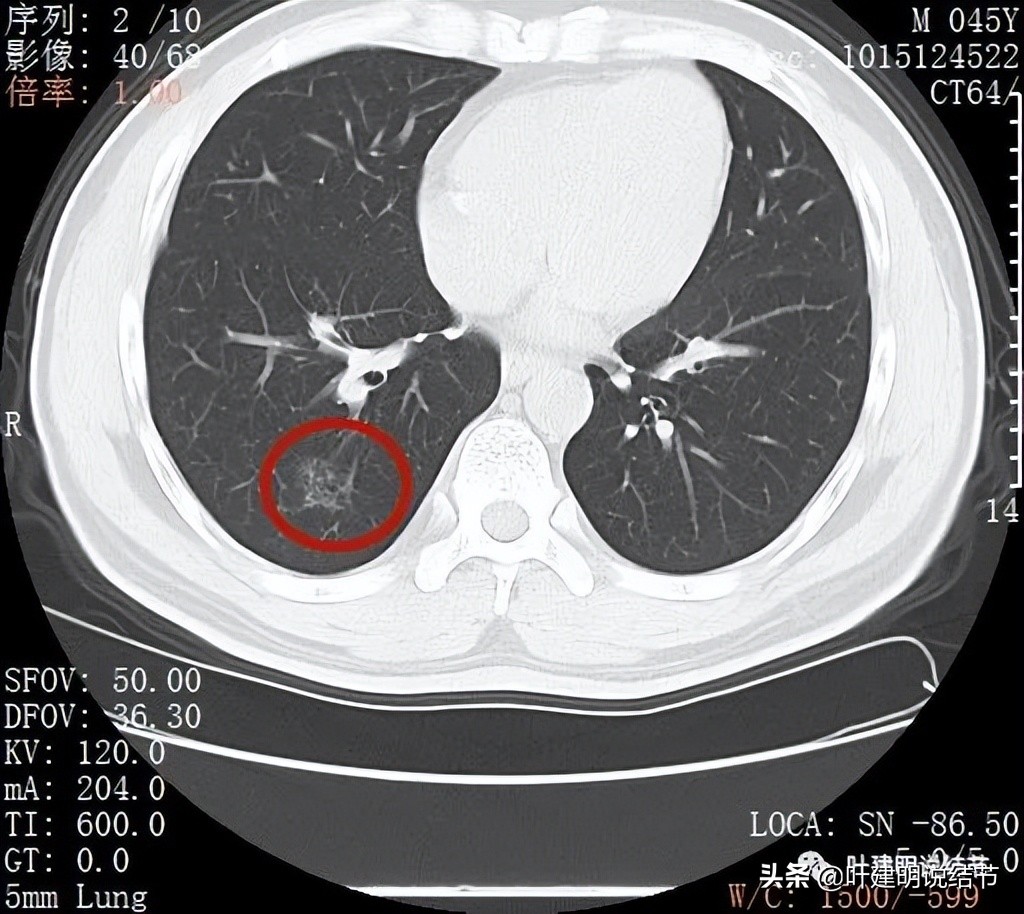

丽水的某A,今年45岁,男性。几个月前检查发现右肺下叶磨玻璃病灶,在当地医院检出后,某市医院胸外科专家看过后考虑恶性可能性大,建议其手术。但他听朋友介绍于2022年2月份来我门诊就诊,予以查了胸部CT平扫加右下叶靶扫描。我们先来看他当时的影像:

2022年2月平扫:

右下叶淡而散在的磨玻璃影

整体轮廓有点清楚,似见血管走行于病灶处

密度略不均